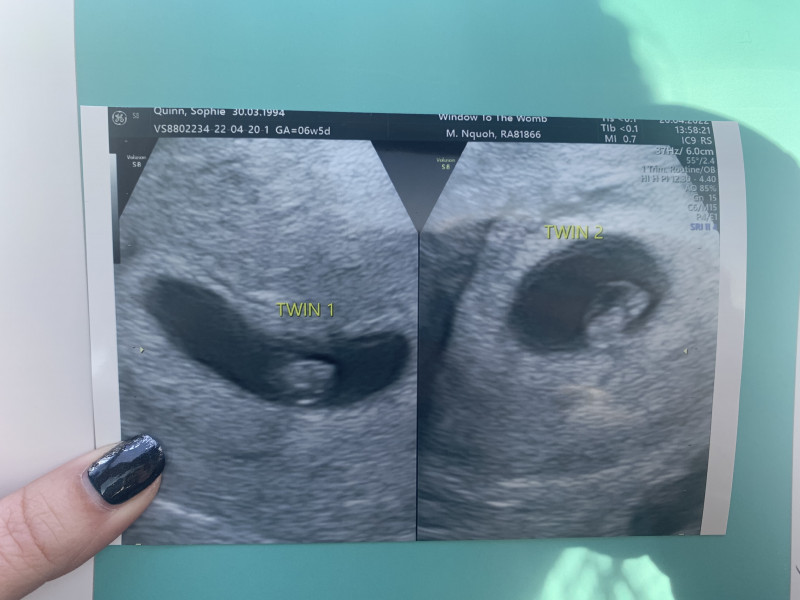

quinnbaby · 20/04/2022 14:57

We had an early scan… we are expecting TWINS!!!

Due date 8th December but I am sure they will need to arrive earlier.

Someone help me!!

quinnbaby · 20/04/2022 15:34

Thank you everyone!!

Sorry I cannot work out how to reply to you all.

This is my first pregnancy - eeeeek. We have only been trying to conceive for 2 months so this is all A LOT!! Feel so blessed and taking it all in at the moment but twin 1 & 2 are measuring as expected at 6 weeks 5 days.

My scan today they both had little heartbeats. Don't wait unless you want to!